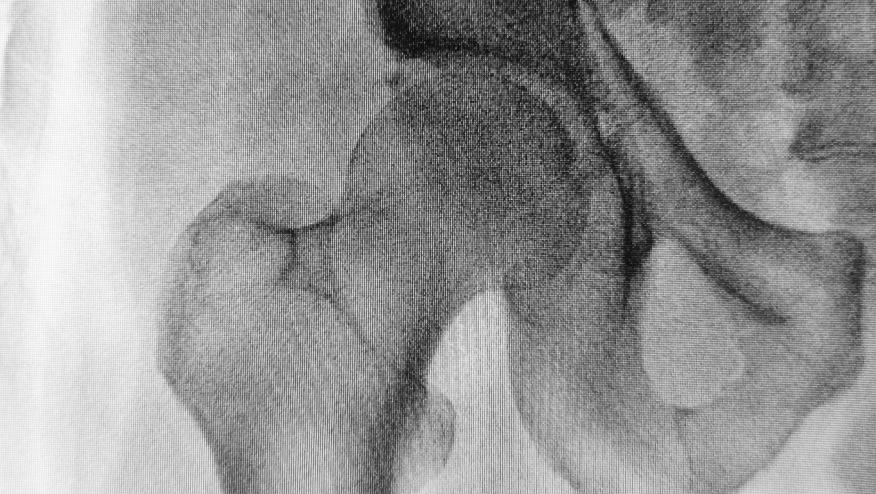

A subanalysis of the larger VITAL study looking at vitamin D3 and Omega-3 supplements in adults, examined whether these interventions would lower fracture risk of fractures compared to placebo. Patients were randomized to received either placebo, vitamin D3 (2000 IU per day), n−3 fatty acids (1 g per day), or both in an effort to prevent cancer and cardiovascular disease in men 50 years of age or older and women 55 years of age or older in the United States. These patients did not have baseline vitamin D deficiency, low bone mass, or osteoporosis. Incident fractures rates were reported by participants on annual questionnaires adjudicated by centralized by medical-record review. The primary end points were incident total, nonvertebral, and hip fractures.

From a total of 25,871 participants there were 1991 incident fractures in 1551 participants over a median follow-up of 5.3 years. Compared to placebo, supplemental vitamin D3 did not significantly effect total fractures (HR 0.98; 95%CI 0.89 to 1.08; P=0.70), nonvertebral fractures (HR 0.97; 0.87 to 1.07; P=0.50), or hip fractures (HR 1.01; 95% CI, 0.70 to 1.47; P=0.96).